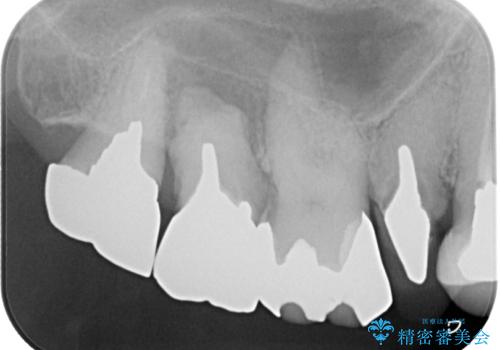

- むし歯の放置期間が長く、クラウンの幅が狭くなってしまった歯を気にして来院された患者様です。

細長いクラウンの周りが汚れてきたこと、奥の銀歯が笑ったときに見えることから、3本をセラミッククラウンにて補綴し、大きさのバランスを整えることとしました。